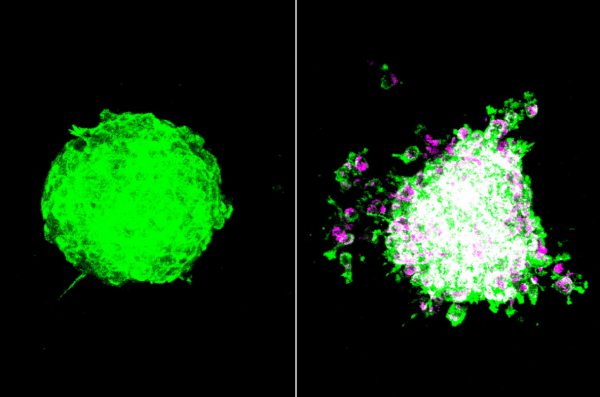

_20221118nid_tumor